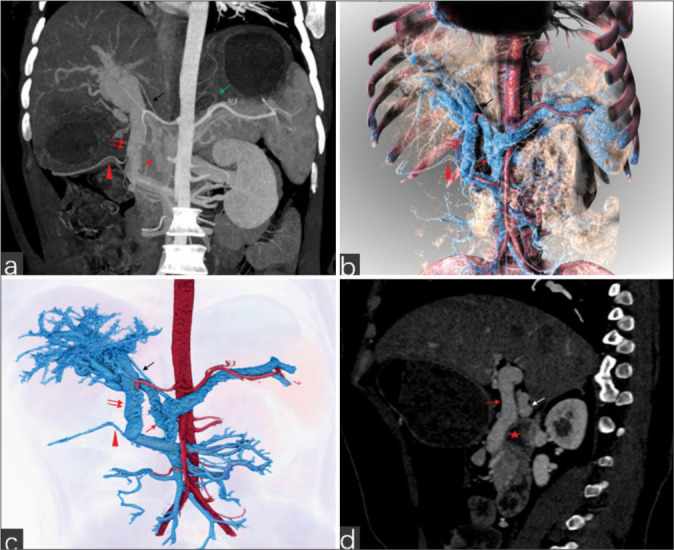

Portal vein (PV) anomalies are rare during embryonic development, with very few cases of duplicated PVs reported. This case reveals a new PV trunk anomaly, where computed tomography venography imaging shows three portal veins. The superior mesenteric vein and inferior mesenteric vein join to form a trunk that divides into two branches: One entering the liver (PV1) and the other ascending to join the splenic vein. The splenic vein then divides into two branches in the neck of the pancreas (PV2 and PV3), both entering the liver. The three PVs vary in thickness and all enter the liver through the first hepatic portal. Understanding the normal structure and anatomy of the PV is important for successful surgical planning. This case involves three main trunks of the PV, which is an extremely rare type of PV duplication anomaly. Reporting this case aims to enhance the awareness and understanding of PV duplication anomalies among clinicians and radiologists.